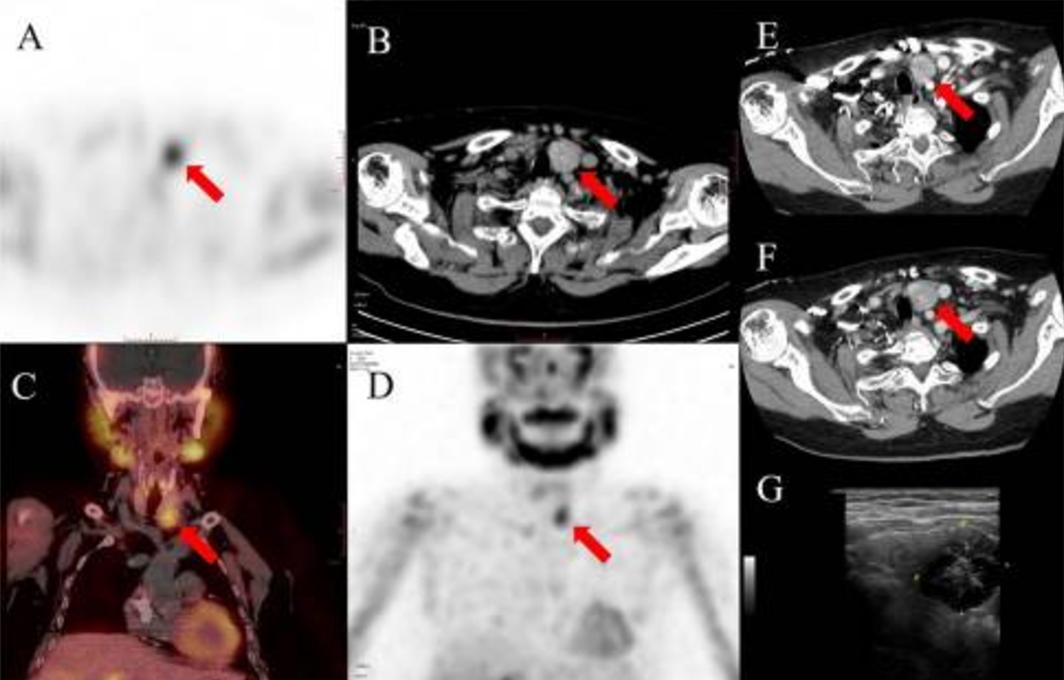

入院时,PTH、血清钙和磷酸盐分别为3356 pg/mL、3.22 mmol/L和1.39 mmol/L。99mTc-MIBI SPECT/CT显示左侧甲状腺下极积聚,与增强CT和超声检查结果一致(图2)。右颈前部皮下有一个示踪剂积聚的结节,与CT结果一致(图3)。

图3 99mTc-MIBI SPECT/CT扫描还显示轻度病灶示踪剂积聚,位于右侧颈部前部皮下低密度结节(红色箭头:a SPECT、B轴位图像、C轴位SPECT/CT融合图像、D冠状位SPECT图像)。对比增强CT扫描显示位于颈前部皮下的轻度增强结节(红色箭头)的动脉期(D)和延迟期(E)轴位图像